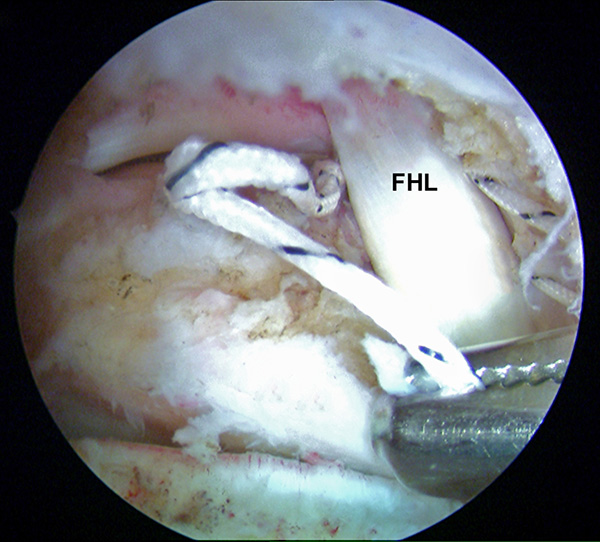

Abbildungen 5-8, Video 2

Anschließend wird die FHL-Sehne angeschlungen. Hierzu wird die Fadenschlaufe über das posteromediale Portal mit einer Fadenzange oder einem gebogenen Klemmchen um die FHL-Sehne geführt und anschließend wieder aus dem Portal herausgezogen. Nach Durchfädeln der freien Fadenenden durch die Schlaufe wird die Schlinge festangezogen. Die Technik wird in Video 2 demonstriert.

Zur Vollansicht bitte die Bilder anklicken. Fotos: M. Galla.